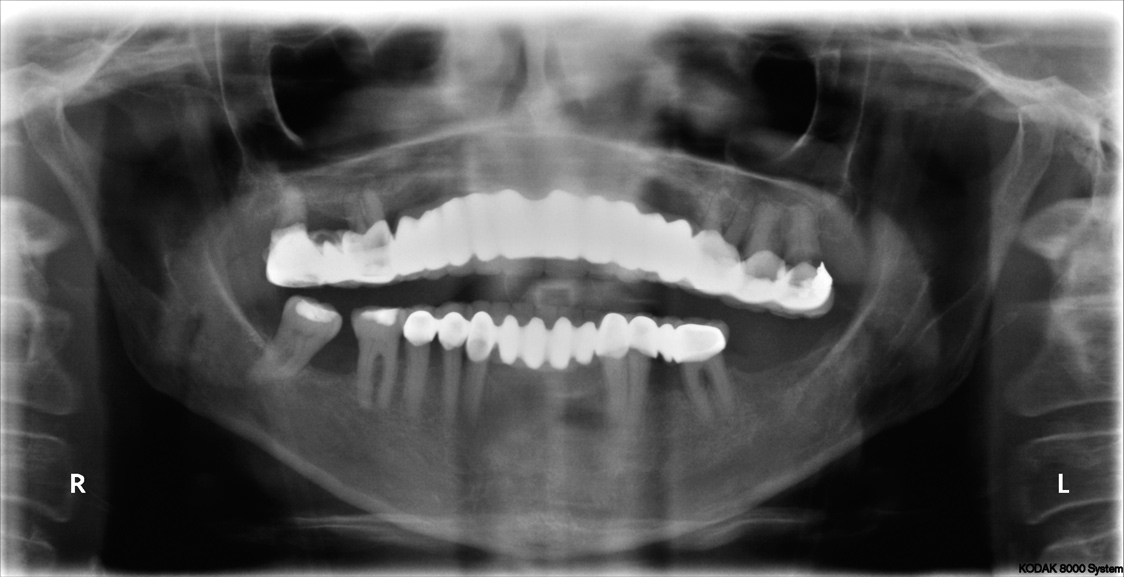

Fig 7. Preoperative panoramic radiograph. Note decay of supporting teeth.

Figure 7